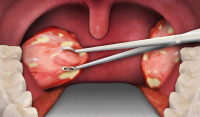

Хоча рак ротової порожнини - це візуальна форма раку, але у 70-80% його виявляють на ІІІ-IV стадіях захворювання.

Смертність протягом 1 року з моменту виявлення поступається місцем лише таким важкодоступним та дороговартісним для діагностики локалізаціям злоякісних новоутворень як рак печінки, рак підшлункової, рак мозку, шлунку, стравоходу.

Регулярні обстеження, тобто, скринінг слизової оболонки рота є важливим кроком для раннього виявлення хвороби, таким чином підвищується успішність лікування до 90%.